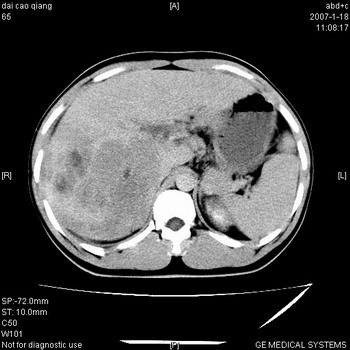

符合巨块型肝癌表现:

1、平扫低密度,增强后表现为快进快出。

2、动脉期可见迂曲的动脉供血血管

3、并可见门静脉右支癌栓形成

4、可见假包膜

5、腹主动脉旁结节影,考虑肿大淋巴结。

典型的肝右叶巨块型肝癌破裂、门脉瘤栓形成。

肝右叶巨大不均匀低密度肿块,前缘有假包膜,增强明显的呈快进快出表现,门脉右支有癌栓,病人虽然年轻但还是首先考虑肝右叶巨块形肝癌,病人血象高只能说有合并感染。不支持肝脓肿。

巨块型肝癌并门静脉右支癌栓

肝右叶巨块型肝癌破裂、门脉瘤栓形成。